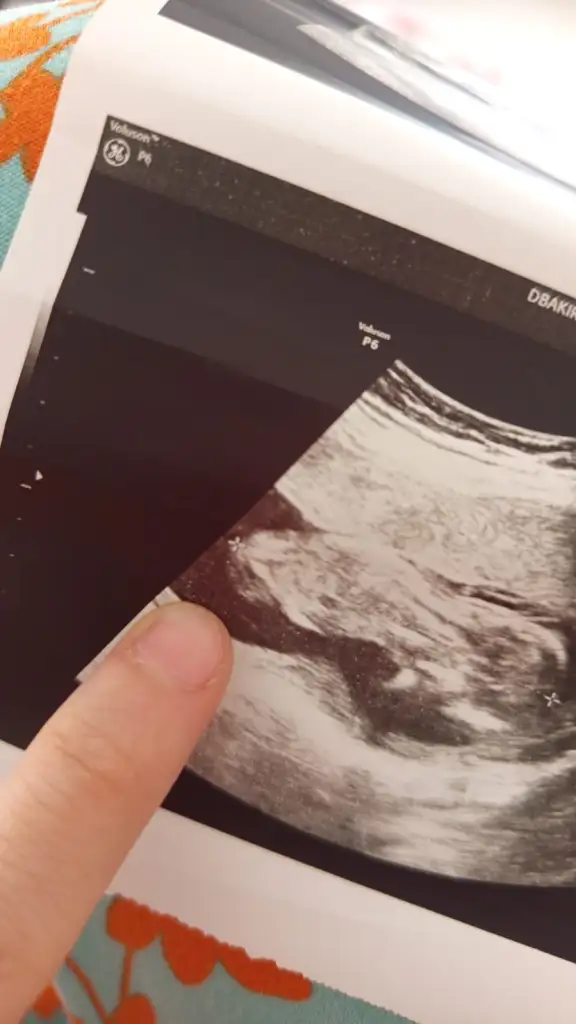

Arkadaşlar merhaba daha önce burada ultrason fotoğrafına bakıp cinsiyet tahmin edenleri görmüştüm benim içinde bi heyecan olur:) var mıdır tahmininiz normalde 12+4 üm ama ultrasonda 13 haftalık görünüyor